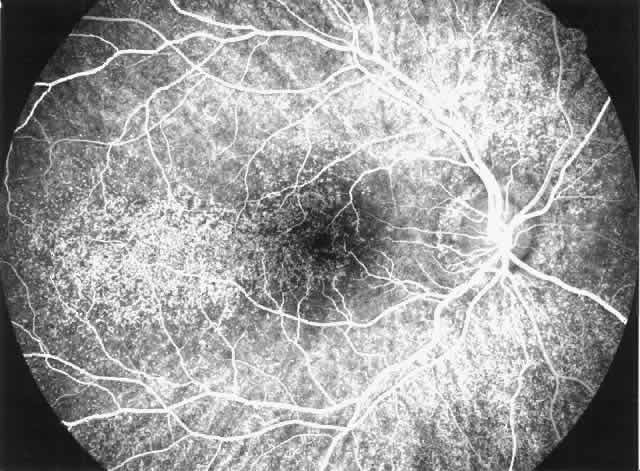

Drusen-like lesions and retinal pigment epithelium damage have also been recognized as a feature of MPGN type II.72–79 In a fluorescein angiographic study of 26 patients who had biopsy-proven MPGN type II, specific fundus lesions were identified in 24 patients (92%).79 Two adolescents with a history of renal disease of 13 months and 2 months had normal fundi. Small-sized lesions similar to small hard drusen were observed in all 24 patients with a history of renal disease lasting for 16 months or more (Fig. 6). In all 15 subjects with a history of renal disease of at least 12 years, larger drusen-like lesions were also noticed. In all 11 patients with renal disease persisting for 18 years or more, drusen occupied most of the fundus and areas of geographic atrophy were seen as well. Foci of new vessels and disciform scarring were observed in eight eyes of five patients with a renal history of 15 years or more (Fig. 7). Most eyes that did not show subretinal neovascularization had normal or nearly normal vision and visual fields. Three patients, however, exhibited ocular symptoms, which were related to pronounced macular atrophic changes, hypertensive retinopathy, and cataracts. The type of fundus lesions was statistically correlated (p<0.0001) with the duration of the renal disease, but not with age, sex, or renal insufficiency. Fundus changes between first and last visit as well as cross-sectional studies suggest a slow progression of retinal disease, which is probably independent of treatment and age of the patient.77–79

Fig. 7. Fluorescein angiographic changes in a 32-year-old patient with renal signs of membranoproliferative glomerulonephritis type II since the age of 9 years. Numerous small and larger drusen-like lesions, atrophic changes, and a small infrafoveolar subretinal neovascular membrane that was successfully treated with argon laser coagulation can be seen. (Leys A, Michielsen B, Leys M et al: Subretinal neovascular membranes associated with chronic membranoproliferative glomerulonephritis type II. Graefes Arch Clin Exp Ophthalmol 228:499, 1990)